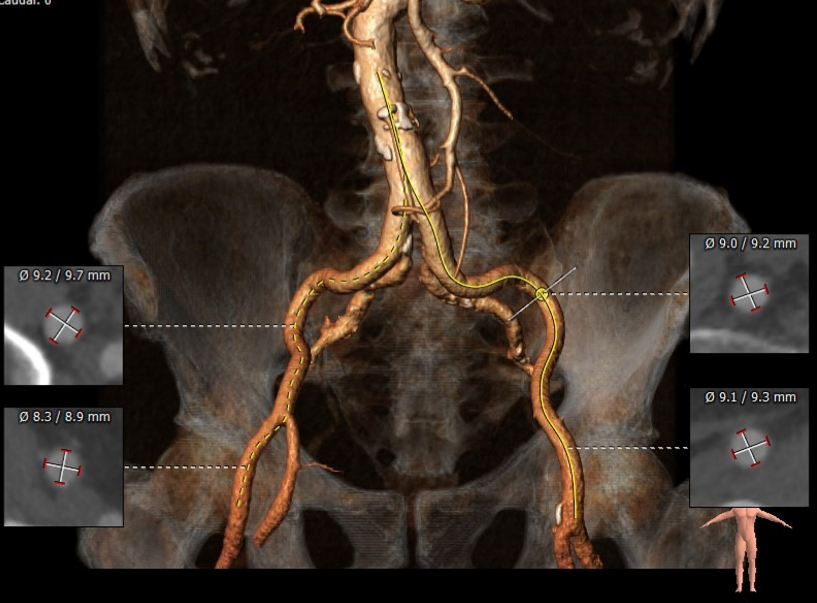

TAVR CT:股动脉入路

1.功能性二叶瓣,右无冠窦融合,重度钙化,左窦小,LCA开口高度9.4mm,极度横位心,心脏角度103°;

2.患者极度横位心,升主动脉及降主动脉3D扭曲,主动脉根部几呈鱼钩样,极大增加输送系统推送及瓣膜释放难度;